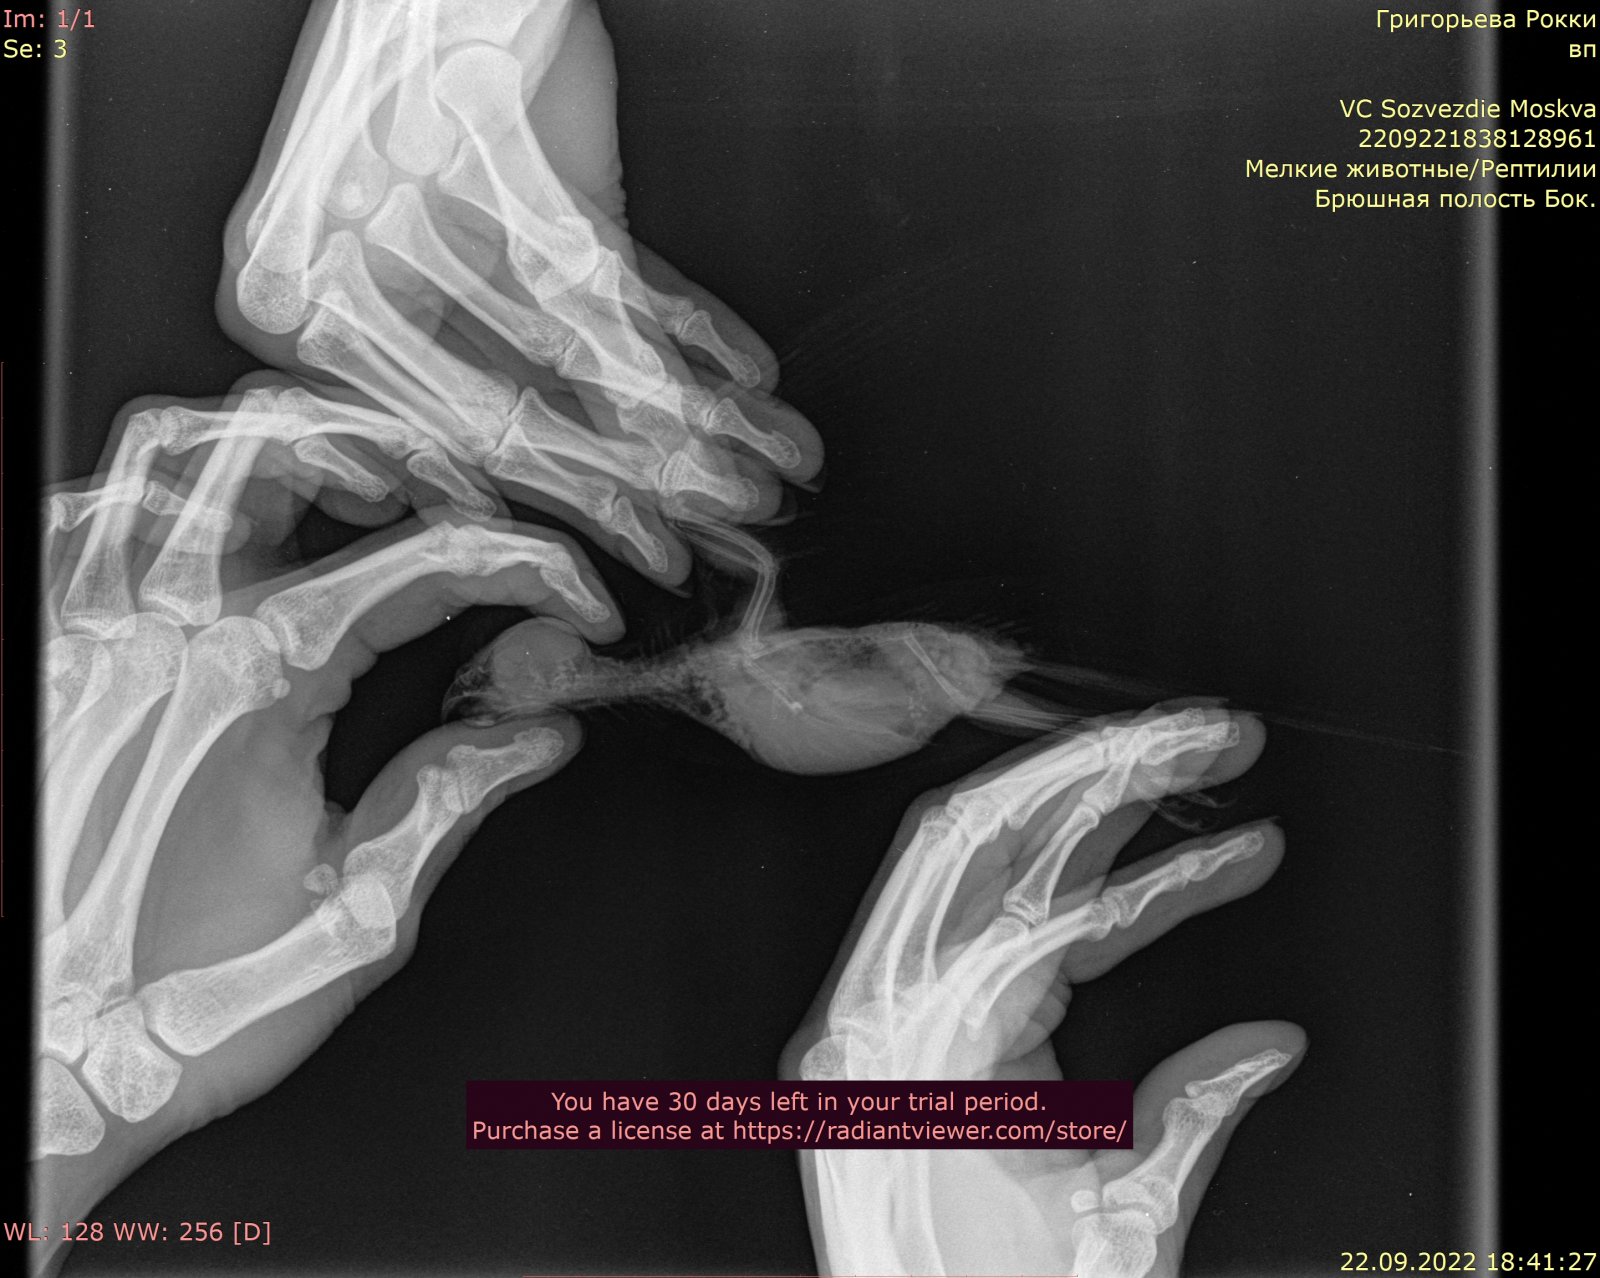

6. Здравствуйте, имеем волнистого попугая с новообразованием семенников. Рентген и заключение врача прикладываю. Читала про такую схему: преднизолон/мелоксикам/ригевидон. Для нас актуально? @Zosia